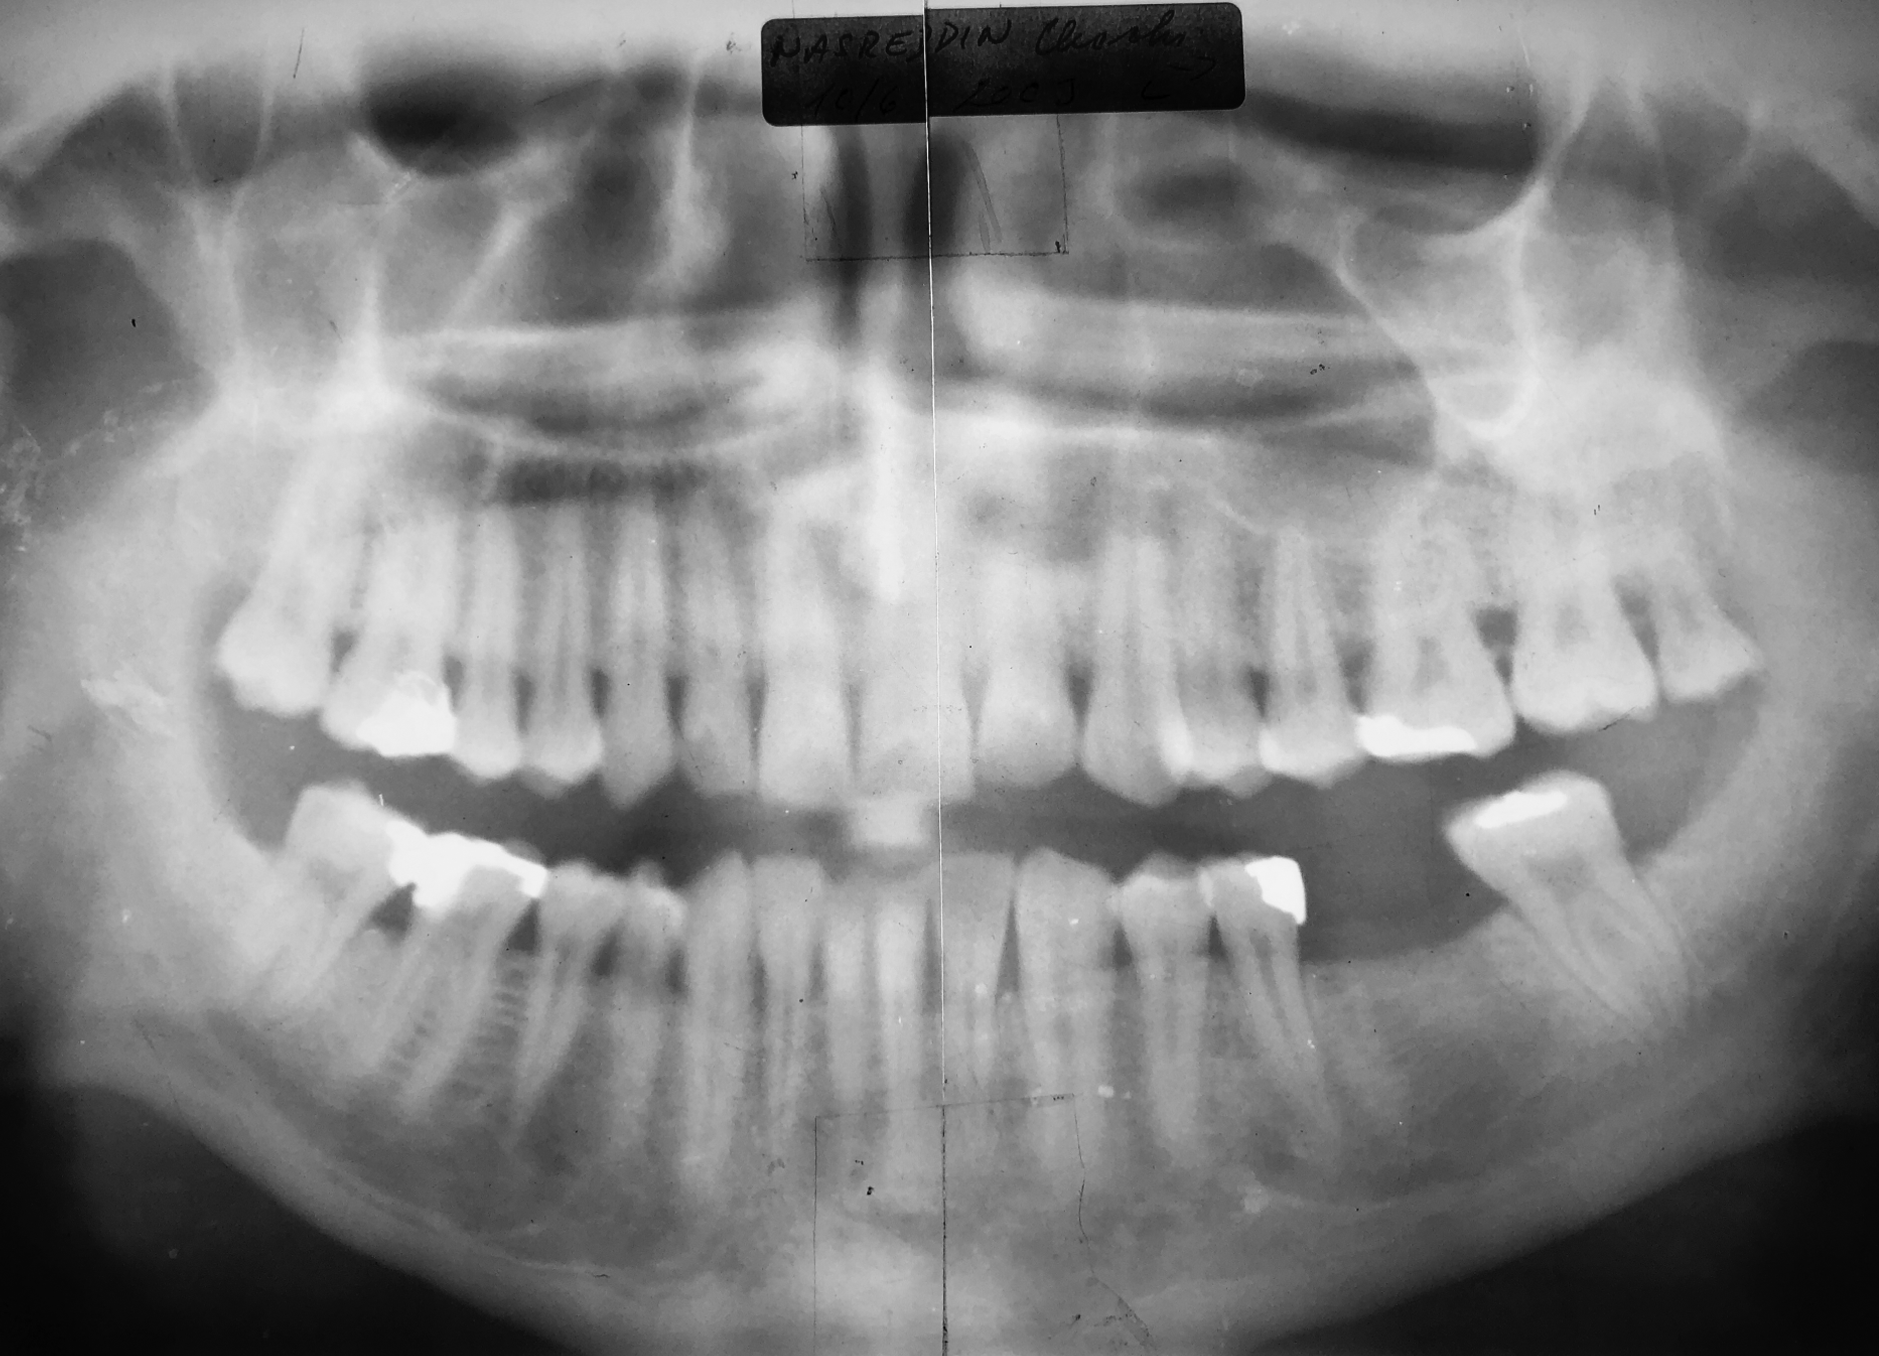

Röntgenaufnahme des ausgeheilten Regio 36 nach dem Eingriff ohne Verwendung von Knochenersatzmaterialien von Juni 2003. Hinsichtlich der Lückenbreite und dem Alveolarknochenvolumen wurden zwei Implantate mit Ø 2,9 mm eingesetzt.

Bei dem Recall im April 2013, nach 10 Jahren in Funktion, war die Versorgung weiterhin perfekt funktionsfähig und die Gewebe um die Implantate waren gesund.